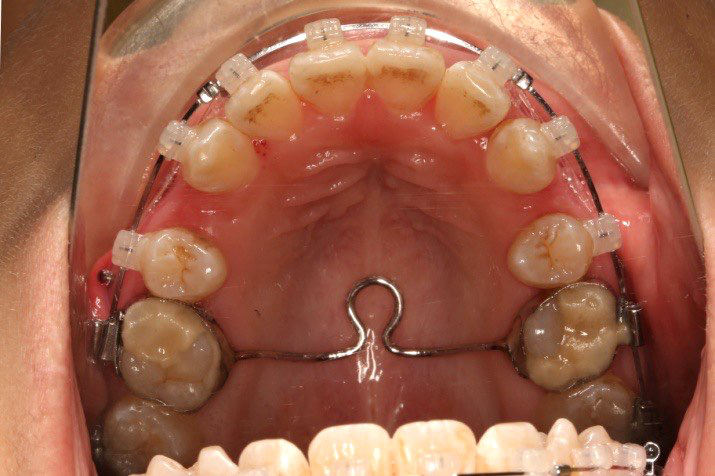

1.第0个月:2016.10.31 ◆ 初戴,0.013cu-niti

2.第2.5个月:2017.1.13 ◆ 上颌加TPA,植入1312-08种植钉,上下0.16cu-niti

2016.10.31  初戴,0.013cu-niti2017.1.13  上颌加TPA,U56间斜形植入韩国庆北1312-08种植钉,上下0.16cu-niti

2017.02.16  上下0.014*25 cu-niti,50g 拉尖牙远中